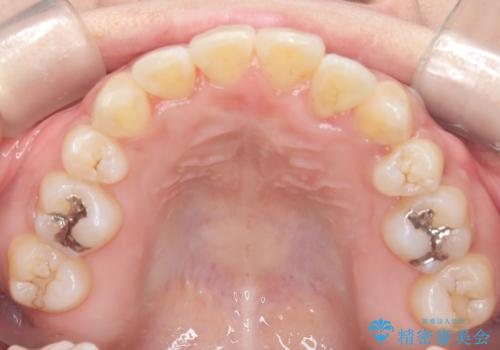

- 患者様は、歯並びのガタガタ(重度の叢生)を改善したいとのことで来院されました。診察すると、歯列のスペース不足が著しく、前歯が重なり合い、噛み合わせにも影響が出ている状態でした。歯をきれいに並べるためには抜歯によるスペース確保が不可欠と判断し、上下の小臼歯4本を抜歯したうえで、目立ちにくい審美ワイヤー矯正(白いワイヤーと透明ブラケット)を用いた治療計画を立てました。

抜歯によって歯を動かすためのスペースを確保。その後、審美ワイヤー矯正を用いて歯を1本ずつ適切な位置に誘導しながら、噛み合わせのバランスも整えていきました。時間はかかりましたが、ガタガタの歯並びがきれいに整い、機能的にも審美的にも満足のいく仕上がりとなりました。患者様からは「歯並びが劇的に改善し、見た目だけでなく噛みやすさも向上した」と喜びの声をいただきました。